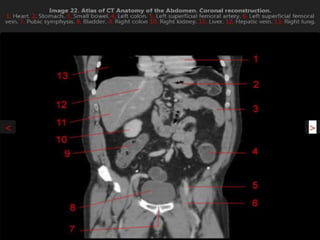

CT cross sectional anatomy.